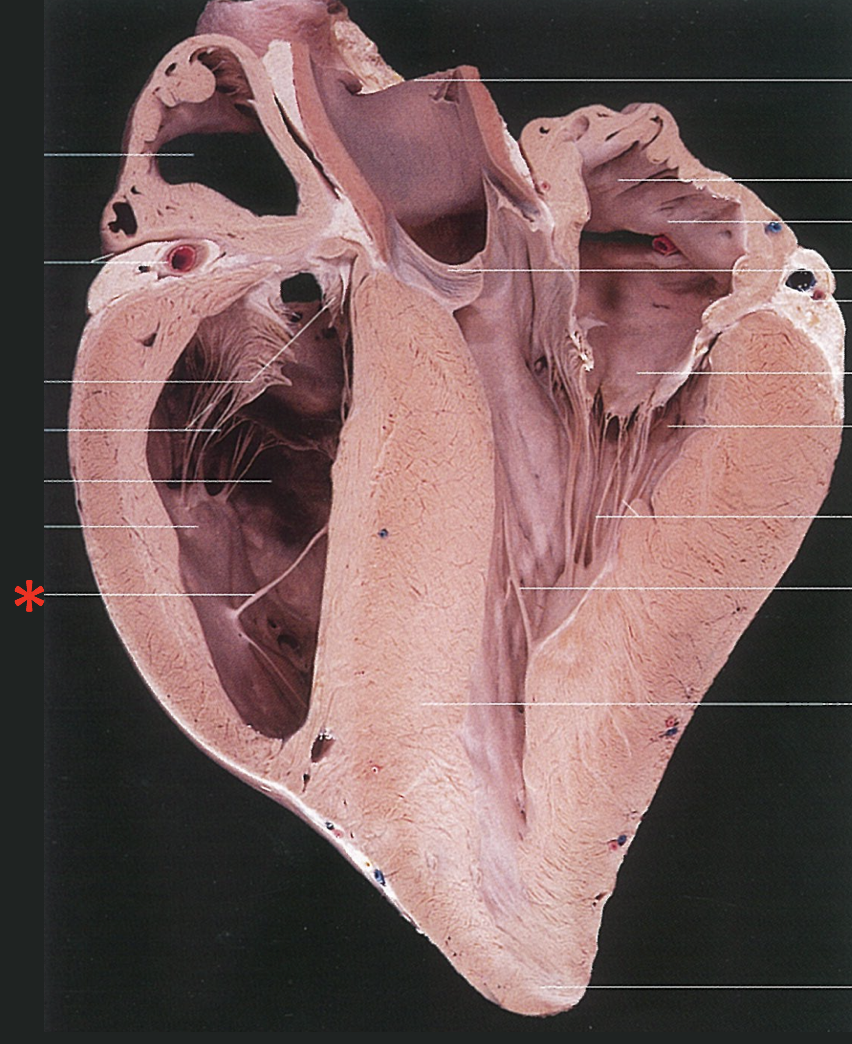

Chordae Tendinae

Left Muscular Band

Right Muscular Band

Muscular Ridges

Left Semilunar Valvula

Parietal Cup

Right Semilunar Valvula

Intermediate Semilunar Valvula

Septal Cusp

Right Ventricular Margin